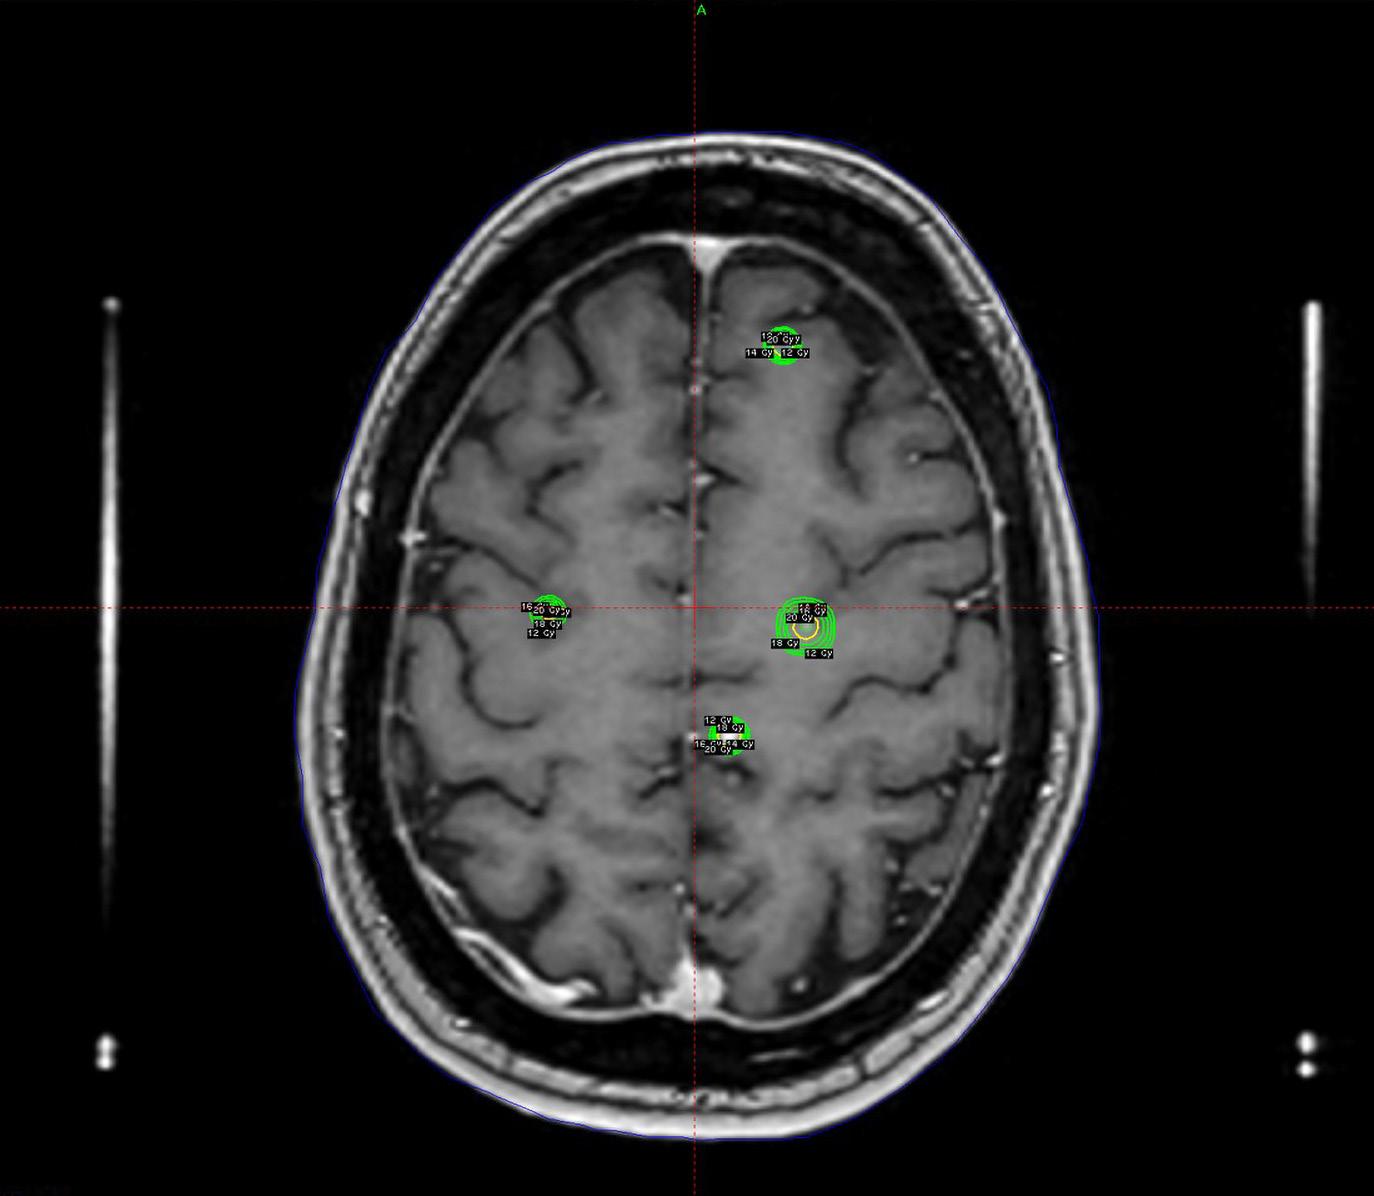

Stråleknivbehandling av hjernesvulst

Utviklingen går raskt. Nye klassifikasjoner, avansert bildediagnostikk og molekylære markører har endret forståelsen av hjernesvulster, men kirurgi er fortsatt en hjørnestein. Forskning fra Norge har vist at tidlig reseksjon gir en betydelig overlevelsesgevinst ved lavgradige gliomer. Ved høygradige gliomer gir omfattende reseksjon bedre prognose, men behandlingen er alltid multimodal og videre framskritt hviler i første rekke på utvikling av mer effektiv onkologisk behandling. Stråleknivbehandling har en sentral plass, ikke bare ved metastaser, men også ved godartede svulster som vestibularisschwannomer, meningeomer og hypofyseadenomer. Hjernesvulster er en ledende årsak til død som følge av kreft i barnealder, og her er det stort fokus på nasjonalt og internasjonalt samarbeid. Presisjon og tverrfaglighet er nøkkelord innenfor alle disse områdene, og utviklingen går tydelig i retning av mer persontilpasset behandling.